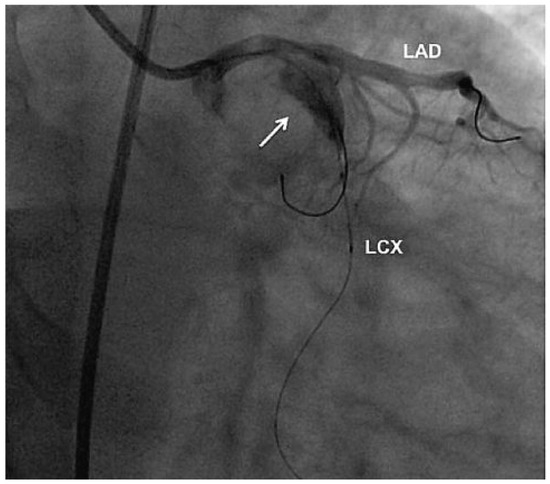

Aneurysm of the Left Circumflex Coronary Artery

by Christian Arranto, Christoph Auf der Maur and Paul Erne

Cardiovasc. Med. 2010, 13(7), 247; https://doi.org/10.4414/cvm.2010.01511 - 11 Aug 2010

Abstract

A 54-year-old man was hospitalised because of an inferior ST-elevation myocardial infarction [..] Full article